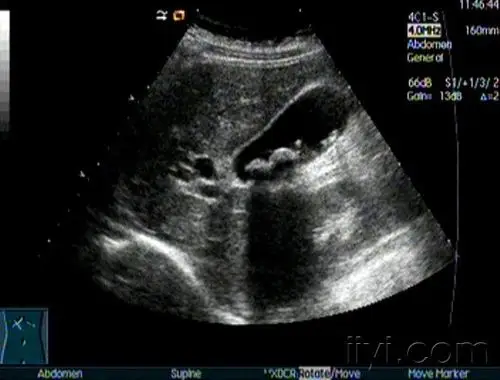

胆总管结石及左肝内胆管结石并肝内外胆管扩张一例 - 超声医学讨论版

胆囊超声图片,在肝胆胰超声中,胆囊结石表现为:胆囊内出现强回声团

14岁胖胖的胆总管小结石声像图 - 超声医学讨论版 - 爱爱医医学论坛

典型胆结石图片 - 超声医学讨论版 - 爱爱医医学论坛